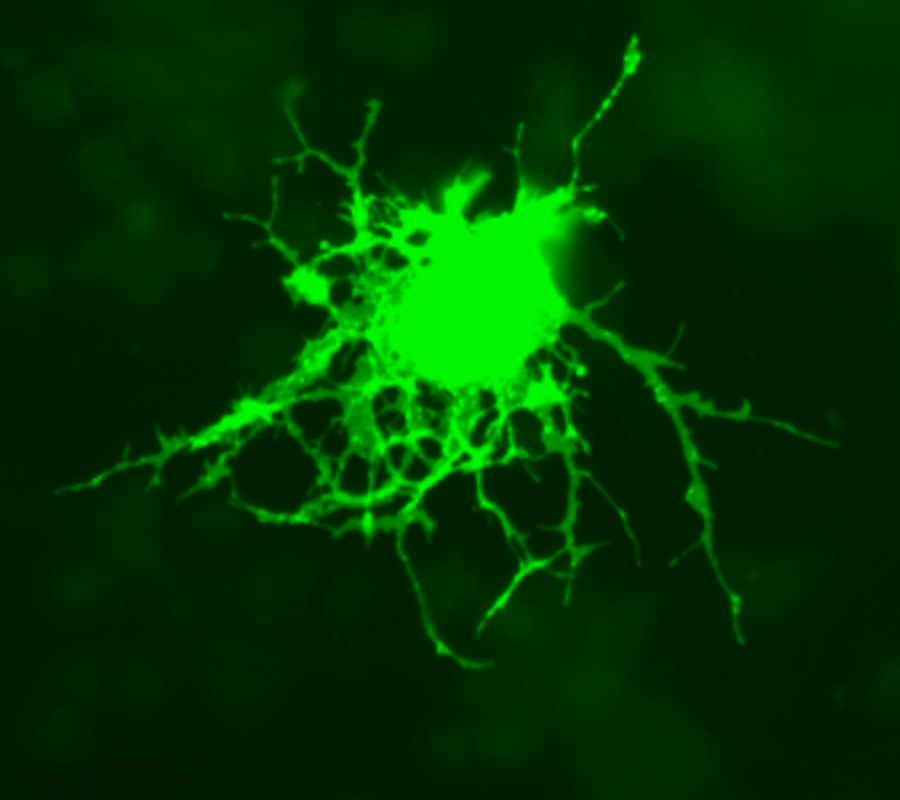

Oligodendrocita, modificato con GFP (Green Fluorescent Protein) - Credit: photo by Jurjen Broeke - Wikimedia - Pubblico dominio

Lo abbiamo dimostrato utilizzando una linea di roditori sviluppata nel nostro laboratorio, in cui le cellule che esprimono GPR17 sono fluorescenti, e quindi facilmente tracciabili nel sistema nervoso durante l'evoluzione della malattia. Nel modello dell’EAE (encefalomielite autoimmune sperimentale), in cui la demielinizzazione è associata a forte infiammazione sia a carico del cervello sia del midollo spinale, le cellule fluorescenti iniziano rapidamente a reagire alle lesioni ma poi rimangono bloccate senza rispondere in modo riparativo. Nel modello del cuprizone, in cui invece la demielinizzazione viene indotta localmente nel cervello con un agente tossico, l’infiammazione è molto minore e i progenitori reagiscono prontamente e riescono anche a portare a termine la maturazione, fornendo quindi nuovi oligodendrociti che contribuiscono alla rimielinizzazione.